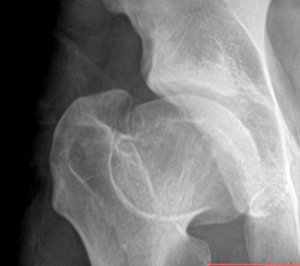

Radiographs of the left hip reveal widening and flattening of the femoral head (coxa plana), widening of the proximal femoral neck (coxa magna), and a thin curvilinear sclerotic line extending across of the femoral neck (“sagging rope sign”). These findings illustrate the classic appearance of the advanced healed stage (stage 4) of Legg-Calve-Perthes disease (LCPD). Note that the acetabulum is usually of normal contour without femoral head dislocation/ subluxation; this is an important differentiating factor when comparing LCPD to congenital dysplasia of the hip, in which acetabular flattening and femoral subluxation/ dislocation are typical findings.

There are several classifications systems used to classify the stages of LCPD; however, this paper will use the Waldentrom classification, which refers to the associated radiographic findings for each stage. The initial stage (stage 1) results from infarction, which produces a smaller and sclerotic epiphysis with medial joint space widening. This stage may be radiographically occult for 3-6 months. The fragmentation stage (stage 2) typically begins with a subchondral lucent line (crescent sign) and then progresses to fragmentation and resorption of bone, resulting in femoral head collapse and patchy sclerotic density. The re-ossification stage (stage 3) occurs as the ossific nucleus undergoes re-ossification in which the necrotic bone is resorbed and new bone replaces. The healing or remodeling stage (stage 4) consists of femoral head remodeling until skeletal maturity. Once fully healed, the remodeled hip has the classic coxa plana, coxa magna, and “sagging rope sign” radiographic features. Dependent upon proper treatment and other patient variables, the degree of resultant deformity will vary amongst patients.